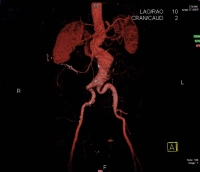

En el ejemplo de película se trata de un AAA infrarrenal cerrado con un diámetro de > 5 cm: